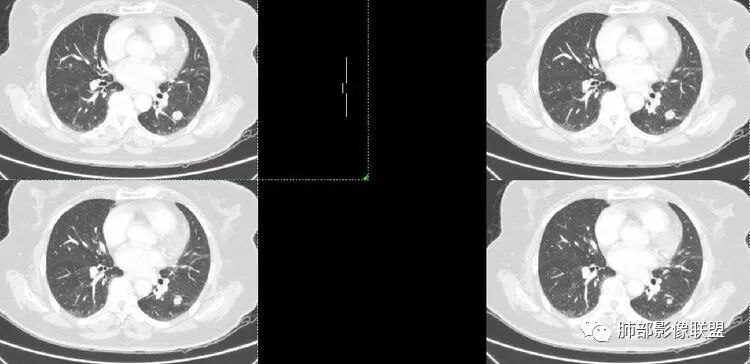

病例资料

胸CT:左下肺实性结节,密度均匀,边缘光滑,未

毛刺、分叶、晕征及棘突样改变,增强可见血管贴边,静脉期较动脉期强化。

诊断:PSP

鉴别:肉芽肿性病变。

患者老年女性,体检发现左肺占位3天。有“高血压”病史。查体无阳性体征。胸部CT:左肺下叶背段类圆形实性结节,边缘清晰,边界光滑,未见毛刺、分叶、棘突等征象,与支气管关系不清,增强中度强化,可见贴边血管征、尾征。综合考虑良性病变,硬化性肺细胞瘤可能大,鉴别孤立纤维瘤、错构瘤。

体检患者,左肺下叶结节病灶,病灶形态规则,边界清晰,内部密度不均匀,可见钙化,增强未见明显强化,考虑良性病变,错构瘤可能。

老年女性,体检偶然发现左肺下叶背段实性结节,边缘光滑,无分叶及毛刺,血管贴边,与支气管无明显关系。内密度欠均匀,似有点状稍低密度,增强后轻度强化,综上考虑良性病灶,错构瘤可能,鉴别PSP。

定位 左肺下叶背段斜裂旁实性小结节,边界清晰,密度尙均匀,未见脂肪钙化,与支气管关系不密切,可见肺血管贴边,增强呈轻中度强化,平扫47hu 动脉期48 静脉期67hu,

定性 常规考虑 良性结节,错构瘤或PSP可能,鉴别类癌,神经源性肿瘤,巨淋巴结增生,建议追观或穿刺活检。

患者,女,63,体检发現左下肺占位3天。

胸CT:左肺下叶背段斜裂旁类圆形孤立实性病灶,边界清晰,密度不均匀,跨度大,内似见脂肪密度,未发现与支气管有关,可见血管贴边,增强呈轻度强化,常规考虑:良性结节,错构瘤可能。鉴别:结核球,周围无卫星灶,无病史,无钙化,不好考虑。其他PSP,类癌,CD等,强化不像。

南边分析

南边 :

血管贴边征一般是有前提的

孤立结节,类圆形,边缘光滑,周围干净

与支气管有关吗?好像显示不明显

与血管的关系?

局部稍推压变

对比同级别血管稍增粗

密度尚均匀

CT值46H

增强67HU

动脉期弱一些,后期强化明显一些

动脉期边缘斑点状、结节状强化为主

后期趋向于均匀强化

动脉期测量区域——中央,不是强化区域

其实强化还算是中度,幅度超过20HU

支持良性

PSP可能 错构瘤待排

病理结果

错构瘤